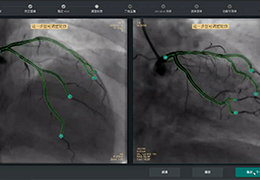

ANYTHINK 经导管主动脉瓣膜置换术分析系统